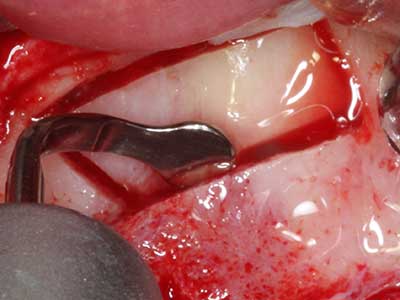

Indication: Preparation near nerves

As noted above, indications for piezo surgery can also be found in the field of conservative dental surgery. Special working tips simplify the exposure of root tips and make it easier to protect nerves and sinus mucous membranes, particularly in the lower premolar and upper posterior tooth regions. Angled diamond tips are used to precisely prepare the resection cavity for the retrograde root filler material for unsealed apical obturation. The ultrasonic technology means the tips can be very slender, which improves the view and the size of the access cavity. As a result, the application of ultrasonic surgery for this indication is one of the standard procedures for apical resection (Del Fabbro, Tsesis et al. 2010, Scarano, Artese et al. 2012).

Indication: Apical resection

When surgical procedures are performed on bone in the immediate vicinity of sensitive structures such as blood vessels or nerves, rotary instruments pose a significant risk of iatrogenic injury. Piezoelectric devices can be helpful for preparation of bone covers and removal of hard tissue close to nerves, particularly for exposure of nerves after iatrogenic injury but also during nerve lateralization for resective and reconstructive procedures or implant placement (Fig. 17-20). Light contact between the piezotip and the nerve does not generally result in damage but proceeding incautiously with saw-like motions or attachments where a residual bone substrate remains may cause temporary or even permanent nerve damage. However, the risk of damage is considered to be substantially lower than when using saws or milling instruments (Pereira, Gealh et al. 2014).